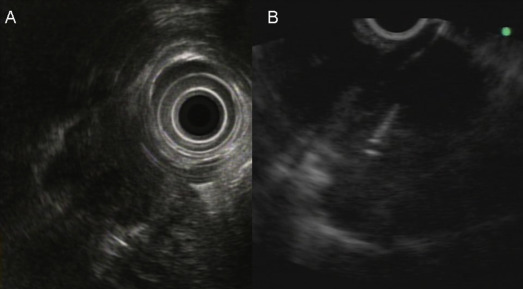

When it was confirmed in the EUS image that the needle had been properly inserted into the lesion, the stylet of the needle was removed and the needle was connected to a syringe with a negative pressure (0∼10 mL). The needle was then moved back and forth > 10 times to obtain a tissue specimen (Fig. 1 ). After withdrawing the needle, the target lesion was observed by EUS to determine whether any changes (shape or internal texture) occurred in the tumor. The adjacent tissue was also carefully observed to determine whether there were any changes, such as hematoma. Because on-site cytopathologic evaluation was not available in our hospital, the needle punctures were repeated several times (2∼5 times puncture when possible) until there was gross evidence that tissue particles had been obtained, or the maximal number of punctures had been performed. At the end of the procedures, absence of bleeding at the point of puncture was confirmed endoscopically. Aspirates were prepared on glass slides and fixed in absolute alcohol solution for the cytological study. When sufficient materials had been obtained, the specimens were also put in the formalin solution for pathological evaluation (hematoxylin-eosin staining and other immunohistochemical stains as necessary).

A patient with pancreatic head neuroendocrine tumor and mediastinal lymph node ...

Figure 1.

A patient with pancreatic head neuroendocrine tumor and mediastinal lymph node metastasis diagnosed by endoscopic ultrasound-guided fine needle aspiration (EUS-FNA) cytopathology. (A) The EUS image of the mediastinal lymph node by radial echoprobe and (B) the EUS image of the performance of EUS-FNA.